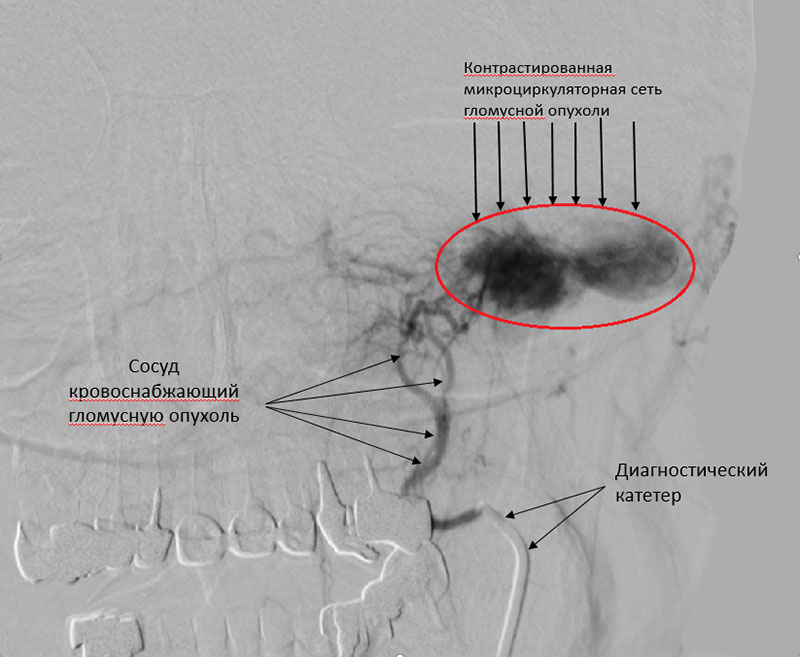

С учетом генеза образования первый этап вмешательства выполнили эндоваскулярные хирурги. Ангиография подтвердила сосудистый характер опухоли, помогла определить размеры, распространенность и источники кровоснабжения. 14.09.2021 произведена эндоваскулярная эмболизация ветвей наружной сонной артерии микроэмболами с положительным эффектом, кровоток в образовании прекращен.

До эмболизации: обильное кровоснабжение очень большой опухоли После эмболизации: кровоток в опухоли прекращен